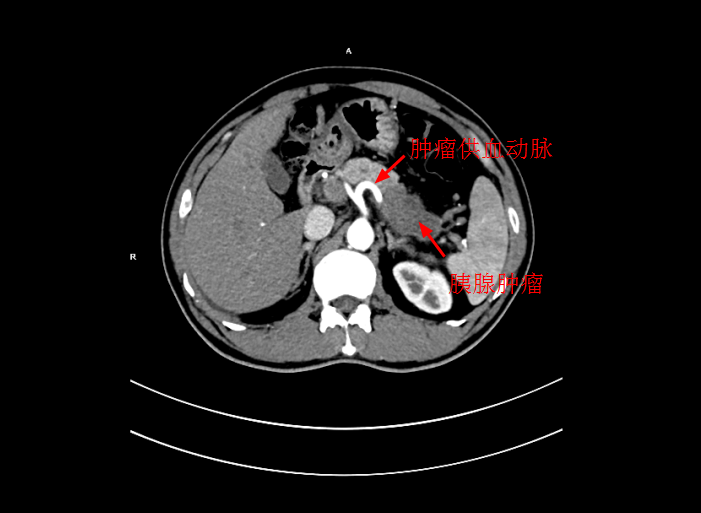

經過檢查後,确診爲局部晚期胰腺癌,大小爲5*3cm,癌細胞已侵犯胃窦。考慮到傳統化療方式,藥物經身體多重代謝後,到達胰腺的濃度低,達不到很好殺滅腫瘤組織的效果,且對正常組織具有一定的毒副作用。爲此李旭丹主任決定給予采用DSA下介入灌注化療,得到患者及其家屬的支持。

4月30日下午,李旭丹主任與胡志華主任上台實施介入化療術,在DSA造影下,清晰可見胰腺腫瘤的供血動脈,專家們将微導管經股動脈穿刺送達瘤體的供血動脈,成功将化療藥物灌注至瘤體,順利完成手術。術後,患者症狀明顯好轉,并于5月4日順利出院。